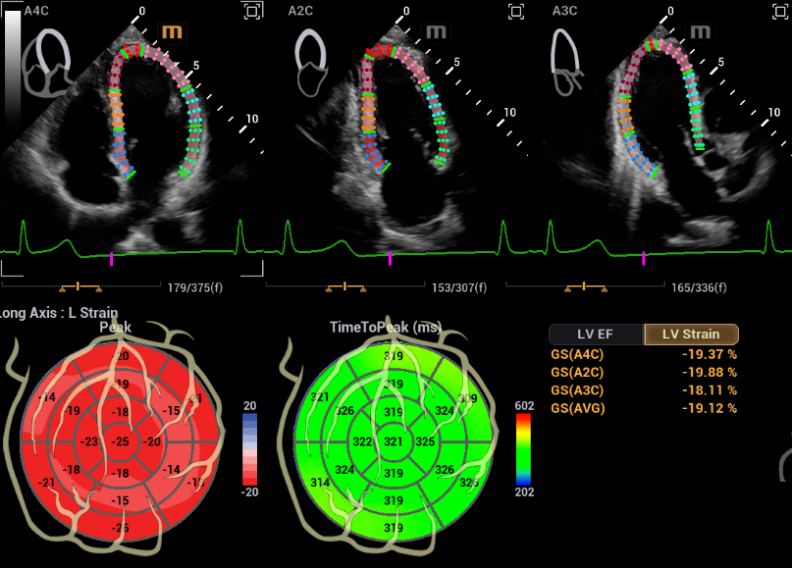

心血管超声诊断系统鲲鹏 Recho R9具有更清晰的心血管影像,更精准的心功能评估

鲲鹏将具备Auto Strain自动应变评估技术,智能化切面识别并追踪室壁运动,高效评估心肌运动状况;还有Auto EF 自动射血分数测量,自动识别心动周期并描迹心内膜边界,计算左室心功能测量参数,评估心脏收缩功能。

中国哪些医疗设备国产权威发布!2023十大自主创新医疗器械_https://www.jmylbn.com_新闻资讯_第38张

Auto Strain自动应变评估技术